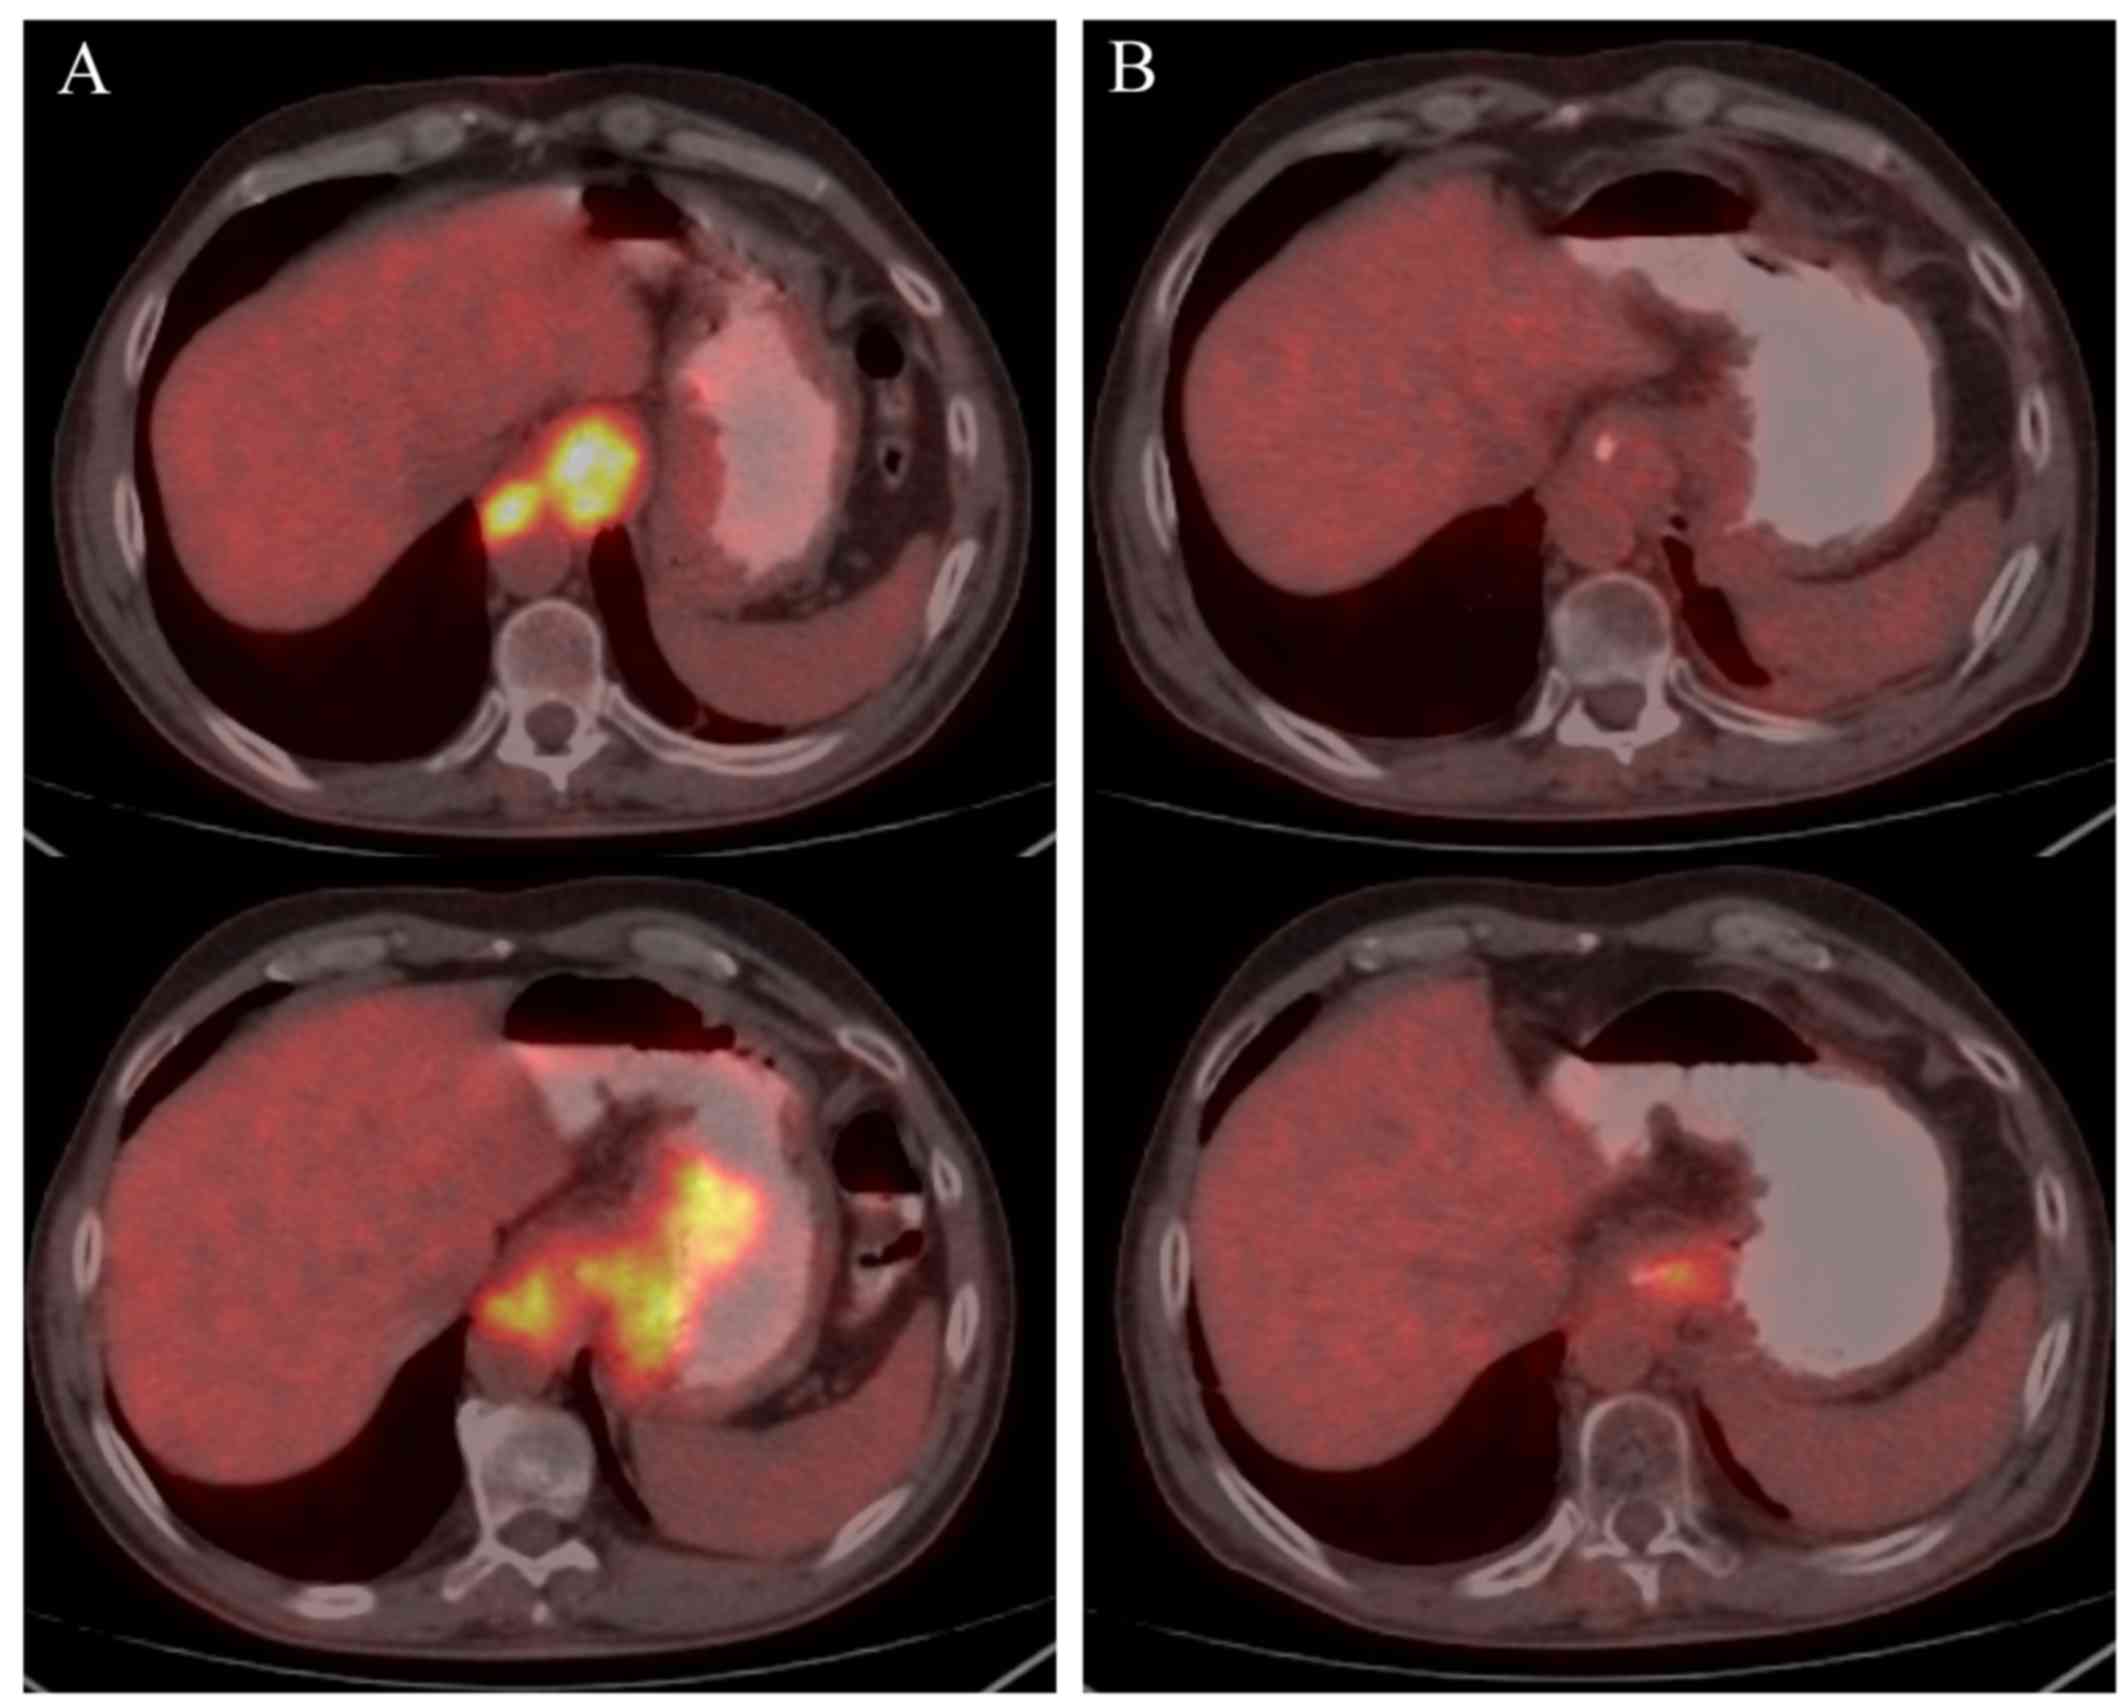

Petct can detect esophageal cancer determine if it has spread assess the effectiveness of a treatment plan and determine if the cancer has returned after treatment. Combining a pet scan with an mri or ct scan can help make the images easier to interpret. A positron emission tomography pet scan detects abnormal cell metabolism to diagnose cancer heart disease and brain disorders before other tests can.

A biopsy is the removal of tissue in order to examine it for disease. So petct is a relatively new very powerful imaging methodology for the diagnosis and staging of a wide range of cancers including esophageal cancer. It can help doctors work out whether tissue is active cancer or not.

Correct integration of petct into the conventional work up of esophageal cancer requires a multidisciplinary approach that combines the information from petct with results of clinical assessment diagnostic ct. For the prevention and early detection of cervical cancer. Petct scans can be useful.